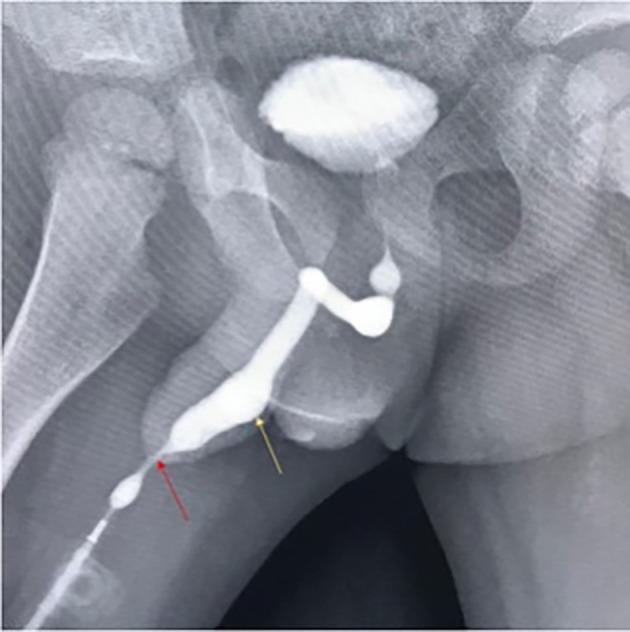

We report the case of a 2-year-old child who presented to us in 2019 complaining of a thin forceful stream, ballooning of the ventral aspect of the penis while voiding, and post-void dribbling. He has a history of undergoing a tubularised incised plate urethroplasty for distal penile hypospadias at 18-months-old. Ultrasound showed increased post-void residual volume and cystourethroscopy confirmed a urethral diverticulum extending from the subcorona to the base of the penis. The patient underwent partial excision of diverticulum, urethroplasty, and meatoplasty. He was followed-up 3 months later with complete resolution of his symptoms and a normal urinary stream with no urethral ballooning or dribbling.

我们报告了一例 2 岁儿童的病例,他于 2019 年来诊,主诉为尿流细弱、排尿时阴茎腹侧球囊状、排尿后滴沥。他曾于 18 月龄时接受过管状切开板尿道成形术治疗远端阴茎尿道下裂。超声显示残余尿量增加,膀胱尿道镜检查证实尿道憩室从冠状沟延伸至阴茎根部。患者接受了憩室部分切除术、尿道成形术和尿道成形术。3 个月后随访,症状完全缓解,尿流正常,无尿道球囊状或滴沥。